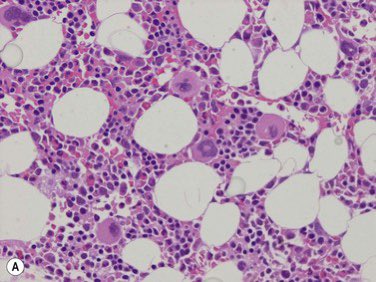

Bone marrow Biopsy

هي خزعة نخاع العظم او قطعة النسيج العظمي الاسفنجي نفسه 🦴

راح تروح على معمل الهيستوباثولوجي وهناك يتم التعامل معاها وتحضيرها وصبغها

وفحصها تحت المايكروسكوب لتحديد الاتي 🔽

📌cellularity

تحديد حجم الخلايا مقارنه ببقية مكونات نخاع العظم زي خلايا الدهون واذا كانت طبيعية مقارنه بعمر المريض

📌Differential

وجود خلايا الدم بانواعها ومراحلها بصوره كافية وطبيعية

📌Abnormalities

ملاحظة اي مظهر غير طبيعي ممكن يدل على عدوى او سرطان